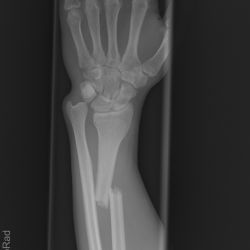

Galeazzi-Fraktur